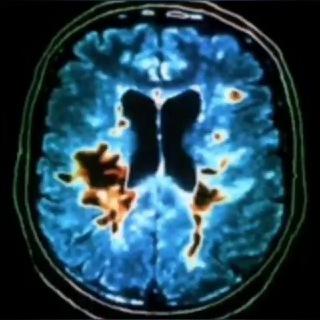

- Рассеянный склероз | Неврология | Медицина | Multiple sclerosis | Neurology | Medicine

Рассеянный склероз | Неврология | Медицина | Multiple sclerosis | Neurology | Medicine